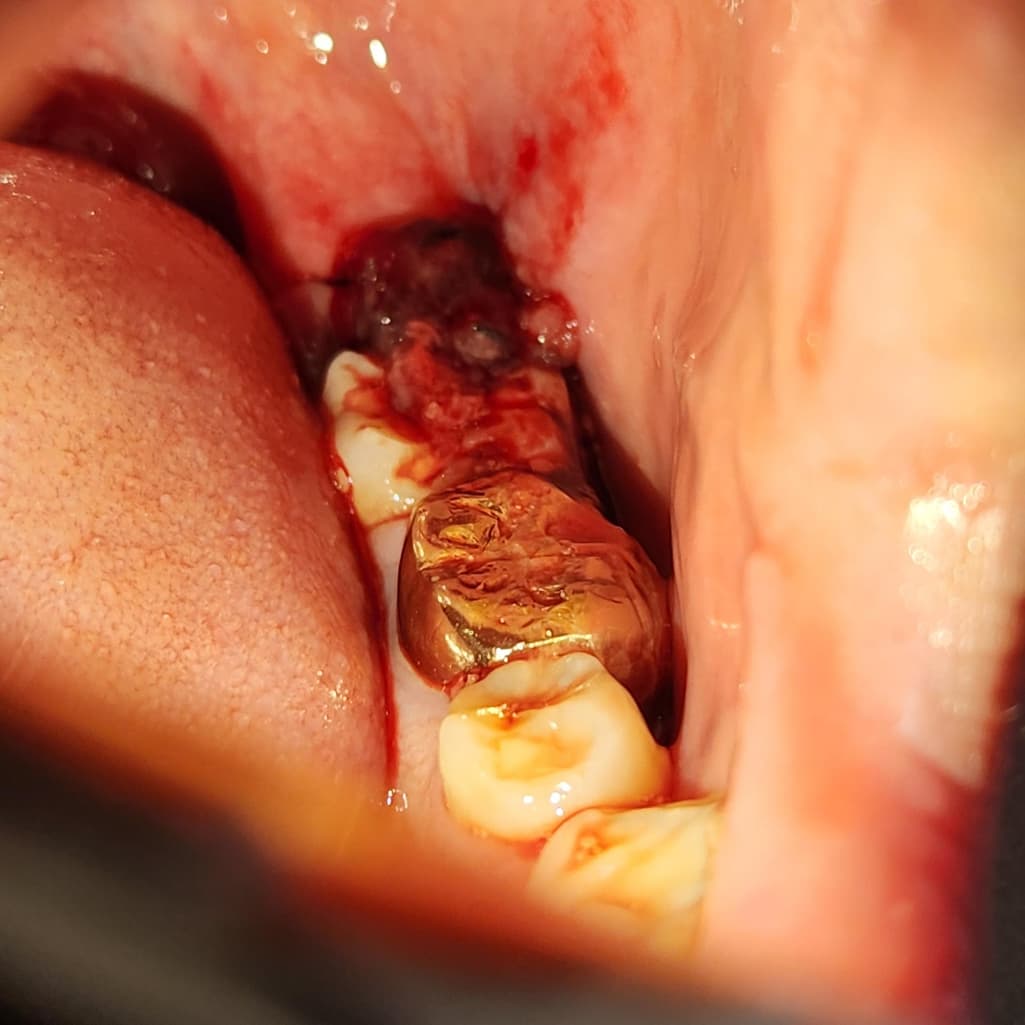

사랑니 발치 후 피가 나는데 확실히 모르겠어요

어제 오후2시에 사랑니를 발치 후 오후7시까지 출혈이 안멈춰서 거즈를 2시간마다 바꾸면서 잤습니다. 근데 오늘 새벽5시에 확인했더니 입 안에 피가 많이 고여있어서 가글을 하고 다시 2시간동안 거즈를 물었습니다. 그랬더니 어느정도 진정된거 같은데 사진을 보시다시피 괜찮은건가요?

그리고 사진 속 맨 끝에 피덩어리로 가려진게 실밥이고, 안보이지만 지렁이 모양으로 피덩어리가 옆에 있습니다. 이것도 원인인가요?

자극이 될 수 있으므로 과도한 가글은 삼가시고요 바깥으로 삐져나온 혈병(피떡)은 어차피 치유에 큰 의미가 없으니 걷어내셔도 됩니다. 지금으로서는 출혈이 있는 것은 아닌 것 같습니다.

거즈를 통해서 더 지혈을 해줘야 할 것 같습니다. 피가 어느정도 나는 것은 문제되진 않습니다.

저정도 출혈 상태라면 지혈이 된게 아니니 거즈를 더 꽉 물고 계셔서 지혈을 시켜주시는게 좋을것같습니다.